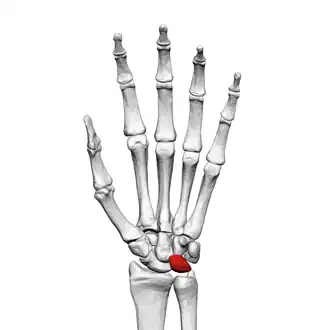

![]() Left hand anterior view (palmar view). Lunate bone shown in red. | |

Lunate bone of the left hand (shown in red). Animation.

The lunate bone (semilunar bone) is a carpal bone in the human hand. It is distinguished by its deep concavity and crescentic outline. It is situated in the center of the proximal row carpal bones, which lie between the ulna and radius and the hand. The lunate carpal bone is situated between the lateral scaphoid bone and medial triquetral bone.

The lunate is a crescent-shaped carpal bone found within the hand. The lunate is found within the proximal row of carpal bones. Proximally, it abuts the radius. Laterally, it articulates with the scaphoid bone, medially with the triquetral bone, and distally with the capitate bone. The lunate also articulates on its distal and medial surface with the hamate bone.[2]: 708 [3]